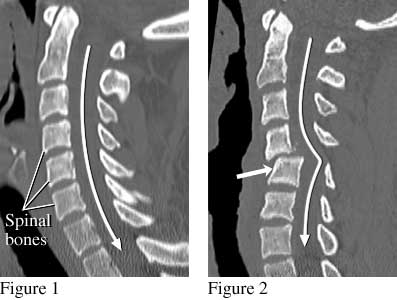

The side view of the spine (figure 1) shows the normal position of the spinal bones. The spinal cord (not visible in this image) follows the path of the long white arrow. Figure 2 shows shifted spinal bones (short thick arrow) from a fracture that damaged the spinal cord. This person was paralyzed after being ejected during an automobile crash while not wearing a seat belt.